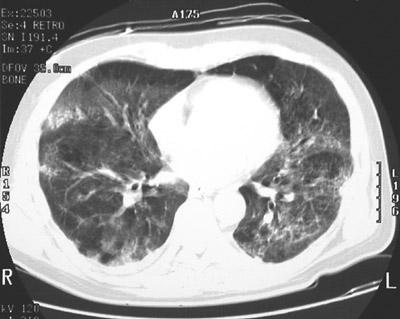

The chest CT scan shown here with the "lung window" setting reveals extensive bilateral ground glass opacifications of the lungs consistent with diffuse alveolar damage (DAD).